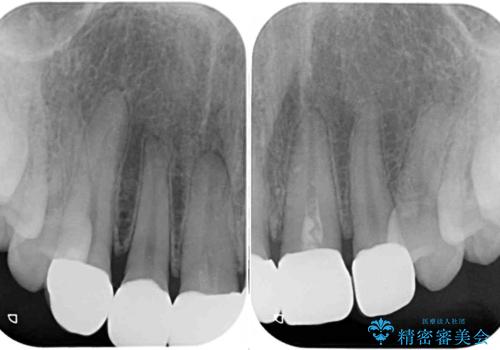

オールセラミッククラウン装着後、レントゲン写真より精度良く装着されていることは確認できているので、日頃のブラッシングで改善させるよう指導しています。